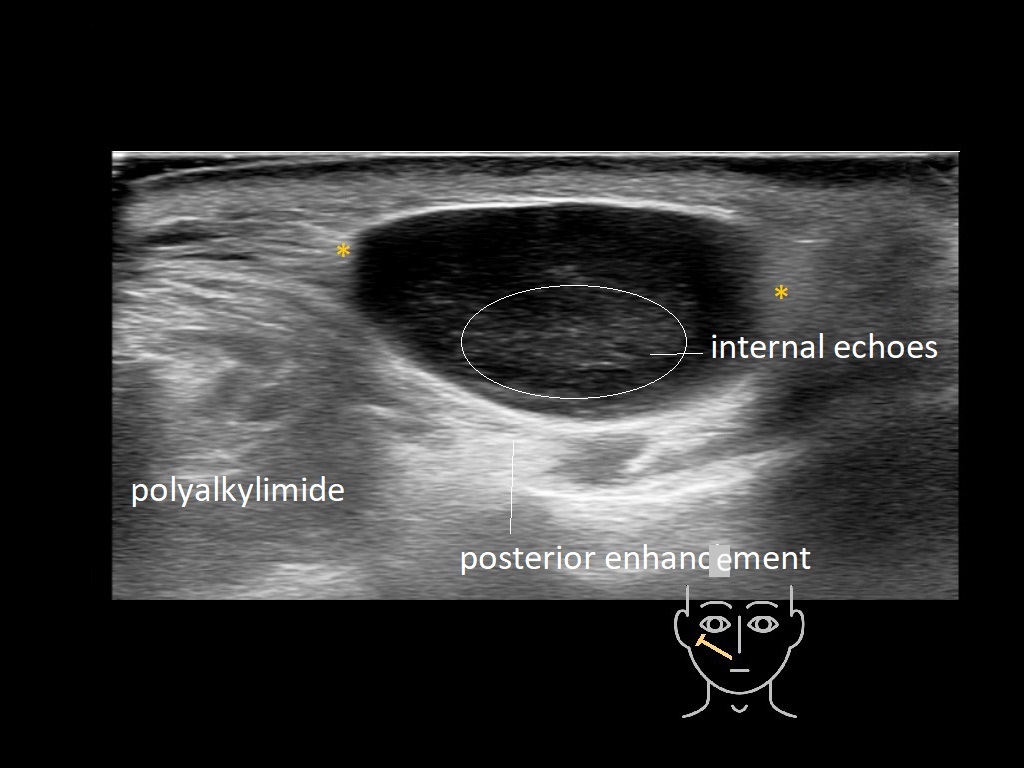

Fillers